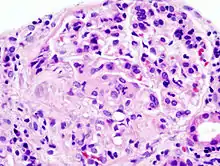

Histopathological image of crescentic glomerulonephritis in a patient with MPO-ANCA positive rapid progressive glomerulonephritis. Hematoxylin & eosin stain.

Rapidly progressive glomerulonephritis (RPGN) is a syndrome of the kidney that is characterized by a rapid loss of kidney function,[4][5] (usually a 50% decline in the glomerular filtration rate (GFR) within 3 months)[5] with glomerular crescent formation seen in at least 50%[5] or 75%[4] of glomeruli seen on kidney biopsies. If left untreated, it rapidly progresses into acute kidney failure[6] and death within months. In 50% of cases, RPGN is associated with an underlying disease such as Goodpasture syndrome, systemic lupus erythematosus or granulomatosis with polyangiitis; the remaining cases are idiopathic. Regardless of the underlying cause, RPGN involves severe injury to the kidneys' glomeruli, with many of the glomeruli containing characteristic glomerular crescents (crescent-shaped scars).[7]